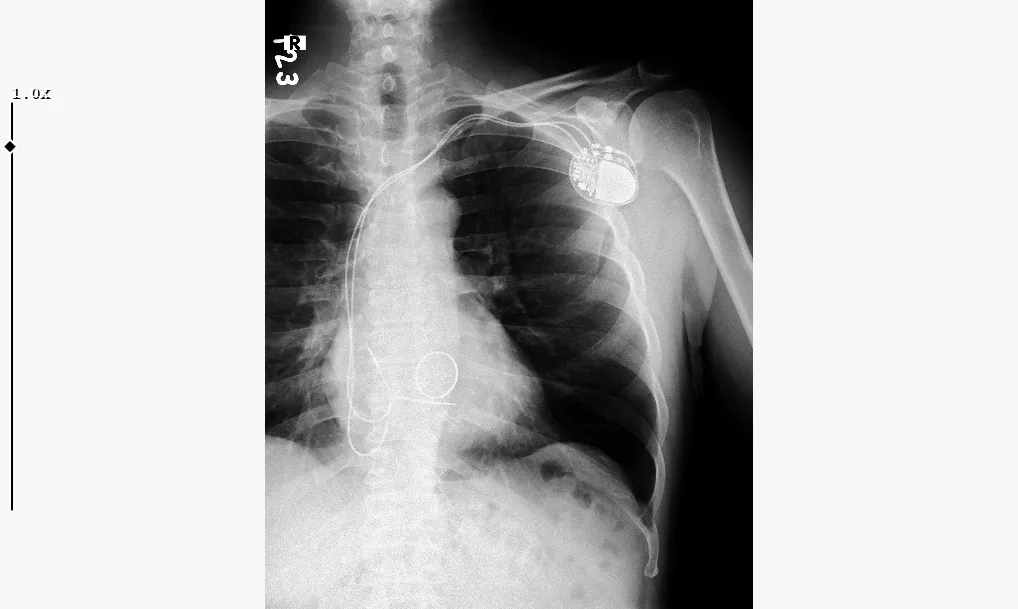

PİLİN KAYDIĞI RÖNTGENDE GÖRÜNTÜLENDİ

Yaşanan yoğun ağrı sırasındaki ani kas hareketleri sonucunda göğse yerleştirilmiş kalp pilinin normal konumundan kayarak sol omuz bölgesine doğru yer değiştirdiği belirlendi.

Bildik'in bu gelişmenin ardından sol kolunu hareket ettirmekte zorlandığı, günlük yaşam aktivitelerini yerine getiremez hale geldiği belirtildi. Durum, röntgen görüntüleriyle de desteklendi. Görüntülerde kalp piline bağlı ince tellerin anormal biçimde kıvrıldığına ve pilin omuz bölgesine yerleştiğine dikkat çekildi.